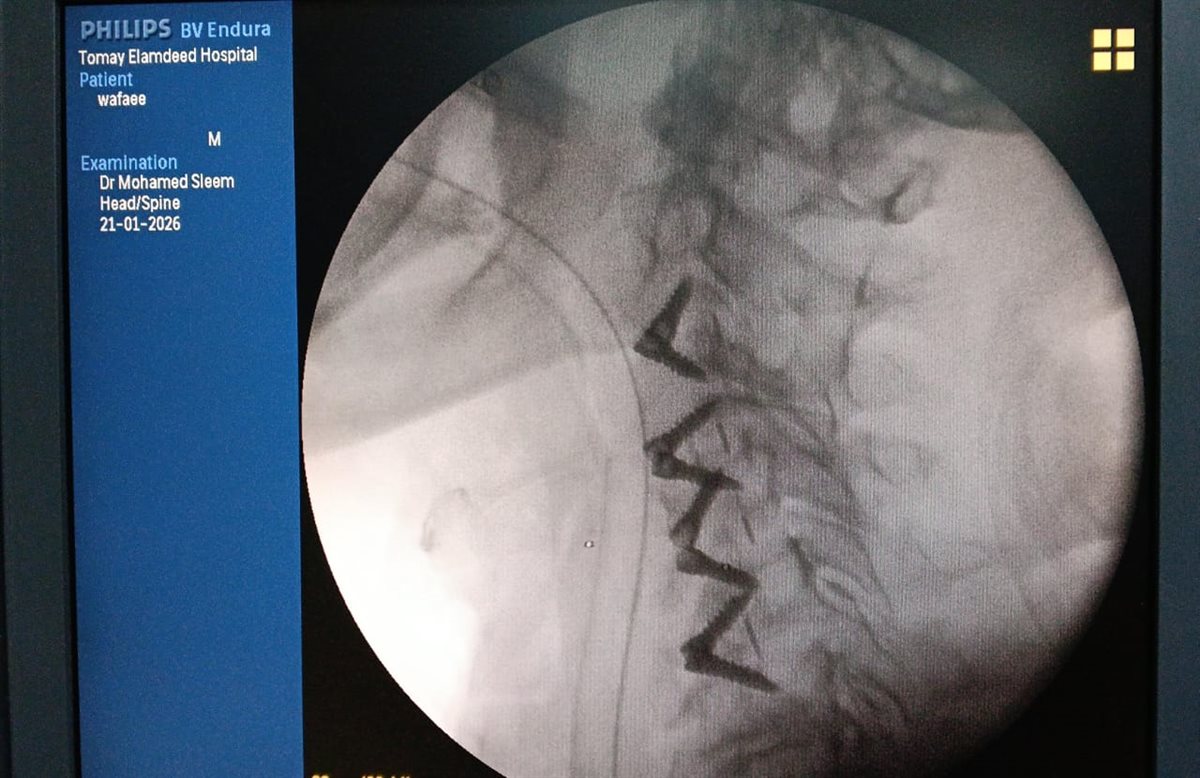

وبإجراء الفحوصات الطبية والأشعات اللازمة، تبين إصابة المريض بانزلاق غضروفي عنقي متعدد على أربعة مستويات، ما أدى إلى حدوث كدمة بالحبل الشوكي وضيق كامل بالقناة الشوكية العنقية، وهي من الحالات شديدة الخطورة التي تستدعي تدخلاً جراحيًا دقيقًا وعاجلًا.

وعلى الفور تم تجهيز الحالة طبيًا من خلال إجراء جميع الفحوصات والتحاليل اللازمة، قبل أن يخضع المريض لجراحة ميكروسكوبية دقيقة ومعقدة، تم خلالها استئصال الغضاريف المنزلقـة، وتركيب أقفاص عنقية مثبتة بدعامات ذاتية (Stand-alone) على أربعة مستويات، وذلك باحترافية عالية، مع خروج المريض من غرفة العمليات في حالة مستقرة وآمنة.